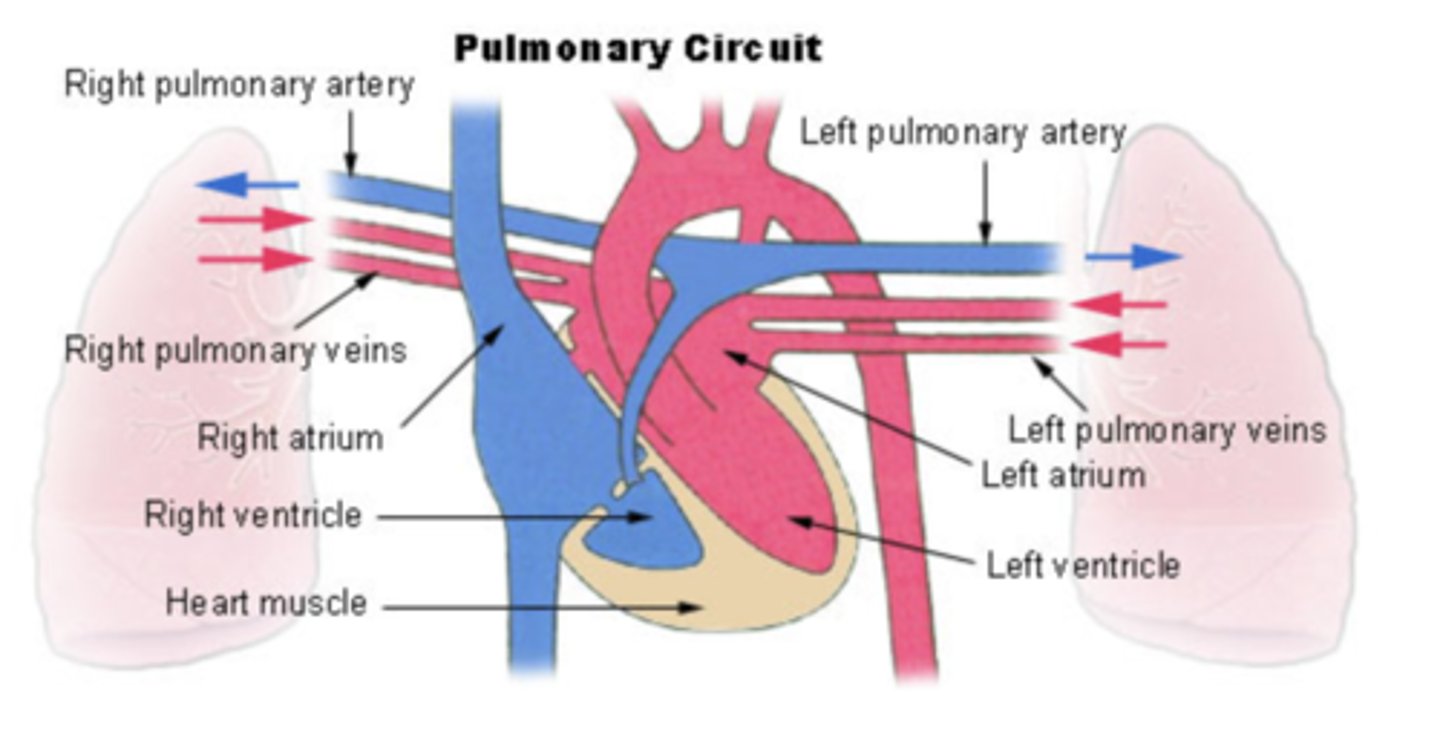

PULMONARY CIRCULATION

Circulation of blood between the heart and the lungs

transports oxygen-poor blood from the right ventricle to the lungs,

where blood picks up a new oxygenated blood

Describe in detail pulmonary circulation

From the right ventricle poor oxygenated blood is impulsed

to the lungs, through the pulmonary artery

blood is oxygenated

returns to the left atria through the pulmonary veins

from where is the right atrium receiving the blood?

From the whole body

Right ventricle pumps blood to?

pulmonary artery

from where receives blood the left atrium?

pulmonary veins